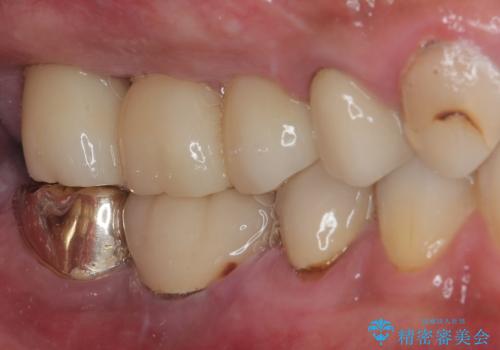

いずれの歯も抜歯が必要な状態であり、抜歯即時埋入によるインプラント治療を行うこととしました。

右上奥歯は骨欠損の範囲が広いため、抜歯即時埋入は可能であっても、即日で仮歯を装着する即時荷重は難しいと判断されたため、手前の歯まで仮歯を装着することとしました。

術後にインプラントの安定値を測定し、十分な値が達成された後、速やかにセラミッククラウンにて補綴治療を行うこととしました。

強い咬合力により歯根破折を繰り返しているため、即日荷重あるいは早期荷重による他の歯への負担を軽減することが重要となります。

抜歯即時埋入インプラントは、咬合力によるトラブルを回避する、非常に有用な手段となります。